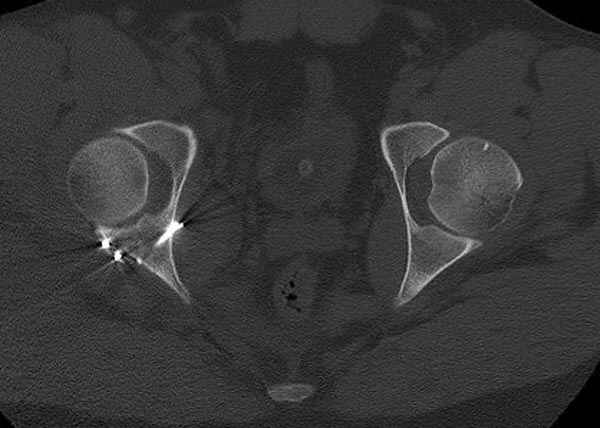

Кроме вывиха виден перелом задней стенки, насчет задней колонны не уверен (видна линия перелома дистальнее ацет. крыши - подвздошная проекция или СТ помогли бы прояснить ситуацию). Поэтому с такой ситуации только закрытое вправление без рефиксации фрагмента задней стенки может привести к рецидиву вывиха (с чем имел неприятность столкнуться не так давно).

На первый взгляд, бедро надо вправить, наложить вытяжение, и дообследовать - Judet views, CT вертлужной впадины, чтобы оценить дефект задней стенки. Вероятно, придется делать остеосинтез заднего края.

5:24 Рентгенограмма таза, вызывают врача ортопеда (снимок N1), его диагноз: закрытый переломо-вывих правого тазабедренного сустава, получает добро на закрытую репозицию в приемном отделении

5:38 Дважды неудачная попытка закрытой репозиции в приемном отделении

N 2

6:20 ответстенный врач принимает решение о репозиции в условиях операционной, предупреждаются родственники и больной, что при неудачной закрытой репозиции, о возможности открытой репозиции и фиксации задней стенки вертлужной впадины.

7:30 начало операции, больной на спине, попытка репозиции после анестезии N3, укладка больного на боку, доступ Kocher- Langenbeck, состояние седалищнего нерва около 2.5см кровоподтек, через joistick головка бедра приподнята, освобовождение сустава, фрагмент заднего края более 3х4 см репонирован на свое место. После промывания

сустава, репозиция вывиха (N4), фиксация фрагмента 2.7(4) мм шурупами и допольнительно реконструктивной пластиной на 8 дырок, фиксация 3.5мм шурупами проксимально и дистально.

Интраоперционные N5 косая запирательная и N6 подвздошный снимок

11:50 больной в послеоперационной, рентгенограмма N7, компьютерная томограмма в тот же день N8-10